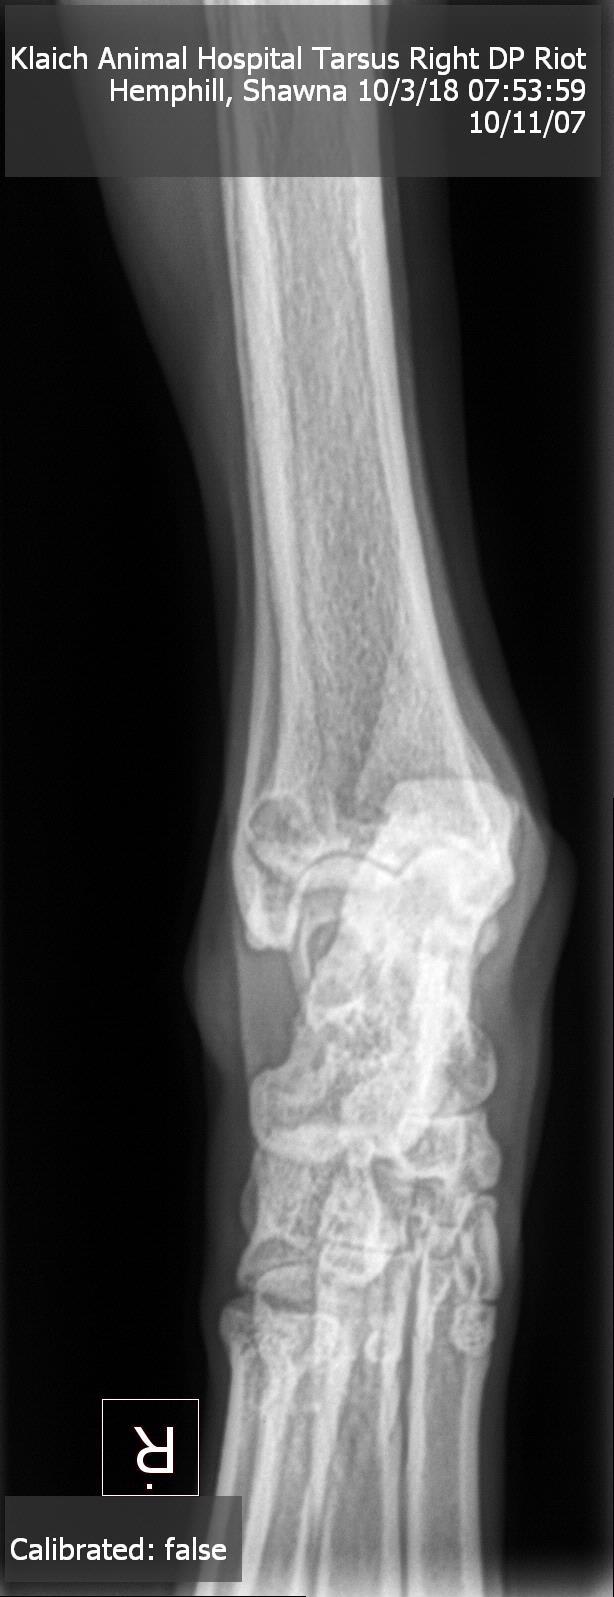

I have an 11 year old black lab. He recently went to a vet for xrays due to limping and weight loss. The vet said he has "moth eaten" bone on his leg so he suggested osteosarcoma. We did an xray of his lungs as well as blood work which both came back clear. What is wrong with my dogs leg?? He still limps badly.

Osteosarcoma can’t be totally diagnosed by an X-ray, and this doesn’t look definitive to me. I recommend taking him to an orthopedic specialist for a second opinion, and they can take another X-ray to compare with this. If it’s bone cancer the moth eaten area will probably be larger or more defined. They can also do a bone biopsy to confirm the diagnosis. He could be lame from a shoulder problem, or even pain radiating down his leg from a disc in his neck. Hopefully he is on pain medication. In my opinion the next step to be sure of the diagnosis would be to get an exam with a specialist. Thanks for using Petco Pet Education Center, formerly Petcoach to help you care for Riot.